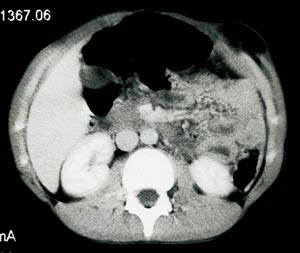

Pasient 1. En tidligere frisk 12 år gammel gutt ble innlagt i lokalsykehus etter en bilkollisjon. På skadetidspunktet lå han sovende i baksetet med setebeltet over abdomen. Ved ankomst i lokalsykehus klaget han over sterke abdominalsmerter. Det var uttalte kontusjonsmerker over et større område av abdomen. CT-undersøkelse viste en stor defekt i fremre bukvegg med herniering av tynntarm (fig 1), diafragmaruptur på venstre side med dislokasjon av milten og venstre nyre til venstre hemithorax samt hemothorax. Pasienten ble overflyttet til Ullevål universitetssykehus, hvor han umiddelbart ble laparotomert. Det ble utført venstresidig nefrektomi, siden nyrestilken var overrevet, sutur av diafragmaruptur og reseksjon av nekrotisk tynn- og tykktarm som følge av krøsskader. En planlagt relaparotomi ble gjennomført påfølgende dag, med ytterligere reseksjon av nekrotisk tynn- og tykktarm, anleggelse av jejunostomi, transversostomi og sigmoideostomi. Bare vel en meter av tynntarmen kunne bevares. Han hadde et komplisert postoperativt forløp og ble respiratorbehandlet i to uker. Fraktur i andre lumbalvirvel ble behandlet med korsett i seks måneder.

Begge våre pasienter ble undersøkt med CT, som tydelig viste bukveggsdefektene (fig 1, fig 2). CT er en god undersøkelsesmetode for å vurdere intraabdominal parenkymskade hos hemodynamisk stabile pasienter som har vært utsatt for stumpe abdominaltraumer, og er den beste radiologiske undersøkelse for å påvise traumatiske bukveggsbrokk (7). CT-undersøkelse gir en nøyaktig avgrensning av defekten og kan identifisere brokkinholdet. Det er her viktig å minne om at kort tid etter skaden kan en hulorganskade være vanskelig å diagnostisere så vel klinisk som ved CT.